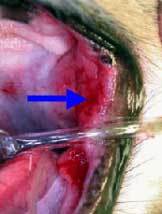

Oronasal Fistula

Oronasal Fistula

Oronasal Fistula

Fistula repaired via flap surgery

Fistula Repaired